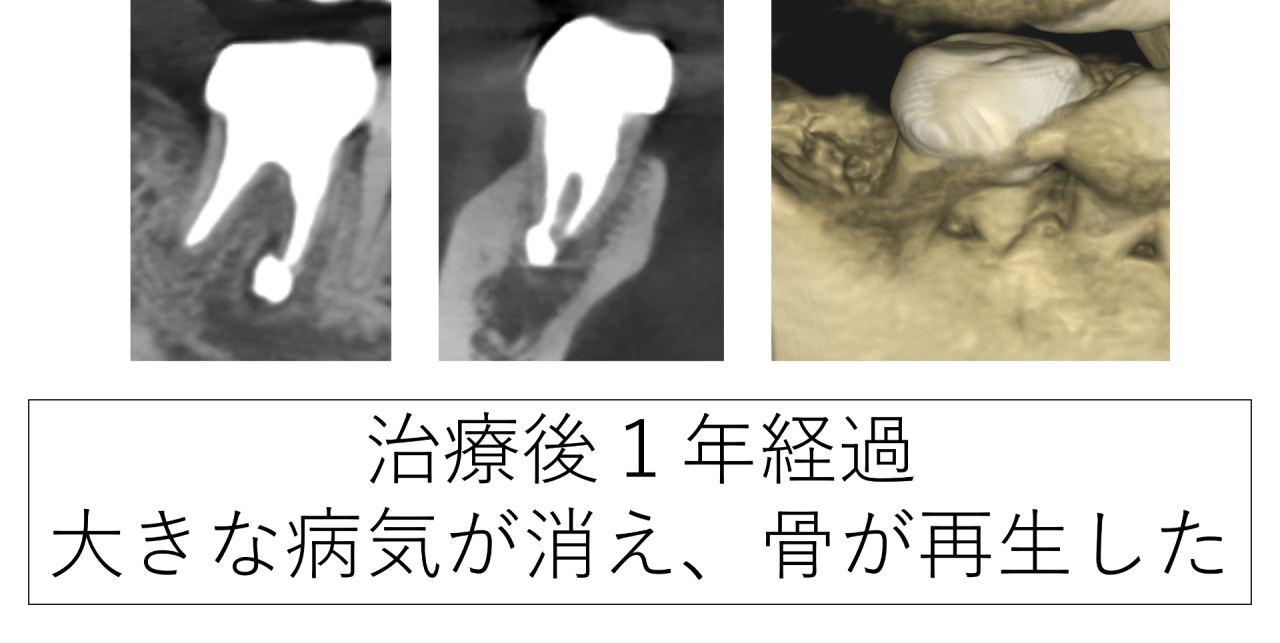

治療後の経過と骨の再生

治療から1年後、溶けていた骨の部分に新しい骨の再生がはっきりと確認され、歯の周囲がしっかりと支えられる状態になっていました。MTAセメントによる特殊根管治療が上手くいったようです。

患者さんも「噛むときの違和感がなくなった」と話され、日常生活において不自由なく過ごせているとのことです。本当に良かったです。

・治療後、骨の再生がレントゲンで確認された